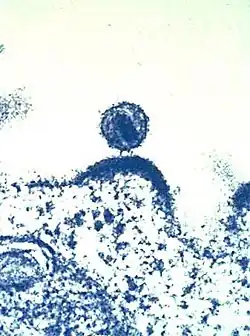

Das Viruspartikel (Virion) hat einen Durchmesser von etwa 100 bis 120 Nanometer und ist damit für ein Virus überdurchschnittlich groß, jedoch deutlich kleiner als zum Beispiel Erythrozyten (Durchmesser 7500 Nanometer). Umgeben ist das umgangssprachlich auch als „AIDS-Virus“ bezeichnete HIV von einer Lipiddoppelschicht, die bei der Knospung von der menschlichen Wirtszelle abgetrennt wurde.[11] Dementsprechend befinden sich verschiedene Membranproteine der Wirtszelle in der Virushülle, beispielsweise HLA-Klasse-I- und -II-Moleküle sowie Zelladhäsionsmoleküle.

Im weiteren Verlauf folgt die Morphogenese, das heißt, über verschiedene Interaktionen finden die viralen Bestandteile wie Gag-, Pro-pol- und Env-Vorläuferproteine sowie die RNA zusammen und formen sich zu zunächst unreifen Virionen, die sich von der Plasmamembran abschnüren. Durch weitere Reifungsprozesse entsteht das reife Viruspartikel, bereit für die Infektion der nächsten Zelle. Zu den Reifungsprozessen gehört insbesondere die Spaltung der Vorläuferproteine – teils durch die virale Protease, teils durch zelluläre Enzyme – in ihre einzelnen Bestandteile, also von Gag in Matrix-, Kapsid- und Nukleokapsidprotein, Pol in Protease, Reverse Transkriptase mit RNase H und Integrase sowie Env in Oberflächen- und Transmembraneinheit. Die neugebildeten Tochtervirionen verlassen die Zelle durch Knospung. Beim Zusammenbau wird das HIV mit dem zellulären Protein Cyclophilin A bedeckt.[101] Dabei bindet je ein Cyclophilin A an zwei Hexamere des Kapsidproteins, wodurch es das Kapsid stabilisiert und maskiert vor intrazellulären Mechanismen der angeborenen Immunantwort in Makrophagen und dendritischen Zellen.[101]